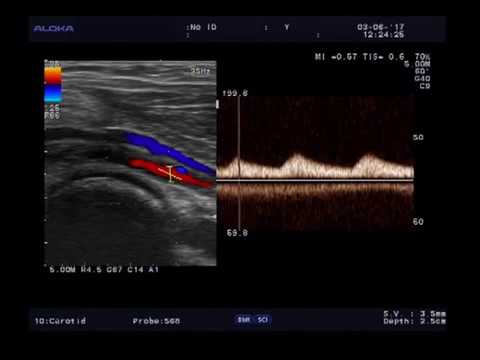

Что такое УЗИ магистральных артерий головы?

УЗИ магистральных сосудов головы (МАГ) — это исследование кровеносных артерий, по которым в головной мозг доставляются с кровотоком все питательные вещества и кислород (сонные, позвоночные, подключичные артерии, брахиоцефальный ствол).